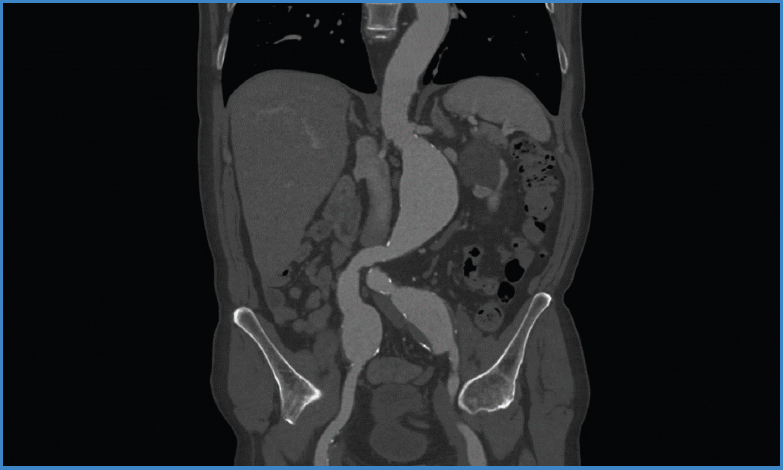

Se presenta el caso de un varón de 83 años, con muchas comorbilidades, en seguimiento en consultas por aneurisma de aorta yuxtarrenal e ilíaco bilateral. Asintomático desde el punto de vista vascular. En la última revisión con angio TC (Fig. 1) se objetivan los siguientes hallazgos:

Figura 1. Angio TC con anatomía del caso: AAA yuxtarrenal y de ambas arterias ilíacas comunes.

• - Aneurisma de aorta infrarrenal que comienza a unos 8 mm de la salida de arteria renal izquierda y se extiende hasta la bifurcación. Presenta unos diámetros máximos de 59 × 55 mm.

• - Aneurisma fusiforme de ilíaca común derecha de unos 38 mm.

• - Aneurisma fusiforme de ilíaca común izquierda de unos 47 mm.

Dados estos hallazgos, se decide la realización de tratamiento endovascular complejo tras llevar a cabo la planificación quirúrgica correspondiente: embolización de arteria hipogástrica izquierda + branch ilíaco derecho + Ch-EVAR.